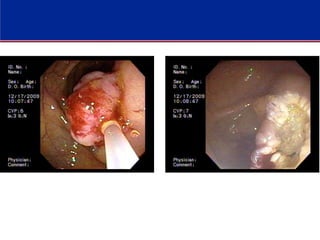

Submucosal Injecion

-Injection of saline or an alternative substance into the submucosa below the polyp

raises the polyp on a cushion of fluid, facilitating endoscopic resection and

potentially decreasing the risk of perforation during subsequent snare excision

-A problem with saline injection is that it is rapidly absorbed. As a result, alternative

agents that are not as rapidly absorbed have been studied (with and without

epinephrine), including hyaluronic acid, dextrose solutions, succinylated gelatin,

and hydroxyethyl starch

Technique

There are two primary goals of colonic polypectomy:

- Complete remove of all neoplastic tissue.

- Retrieval of all tissue sample

Only complete excision of the polyp permits accurate histologic diagnosis